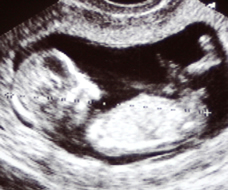

Your baby today

This 2D black-and-white ultrasound scan is similar to the scan you may see and may be given. The baby is the white area, and the amniotic fluid is black. This type of scan is the best way to measure your baby's length at this stage.Your hormones have done all the hard work to establish your pregnancy and as they settle down, so should your nausea.